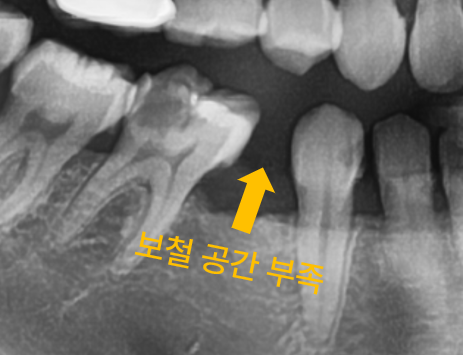

해당 부위는 오랫동안 치아가 없었던 곳으로, 아래의 잇몸뼈는 매우 부족하였고,

빈 공간으로 앞뒤의 치아가 쓰러져서 치아 하나만큼의 공간이 부족한 상태였습니다.

이런 경우에는 임플란트로 회복하기에는 쉽지 않습니다.

특히 뒤쪽에 있는 치아는 충치가 심하게 진행되어 같이 치료가 필요하여

해당 부위는 브릿지 치료를 권해드렸는데요.